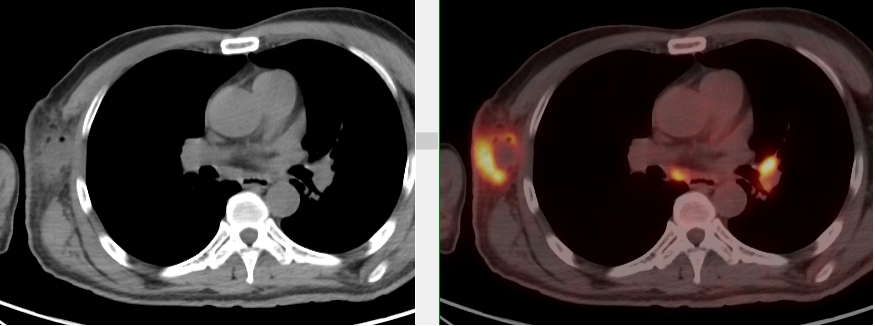

完善PET/CT檢查示:右側腋窩、雙側中下頸部、縱隔、雙側肺門多發(fā)MT,建議淋巴結活檢。后患者行右腋窩淋巴結切除活檢術,經北京大學第三醫(yī)院病理科會診示:右腋窩淋巴結惡性腫瘤,呈淋巴竇內生長模式,瘤細胞呈上皮樣,異型性明顯,伴中性粒細胞浸潤。結合病史及免疫組化,考慮為SMARCA4(BRG1)缺失的胸部腫瘤,伴神經內分泌標記表達。

本例為罕見病理類型的腫瘤,影像學表現無明顯特異性,診斷困難。強化CT和穿刺病理已基本明確為惡性腫瘤,行PET/CT檢查一是為了全身檢查,完善分期,二是根據PET代謝情況指導進行生物靶區(qū)活檢,進一步明確病理診斷。最終,PET/CT除縱隔病變外發(fā)現更多頸胸部淋巴結代謝異常,綜合考慮后對腋窩淋巴結進行切除活檢,最終得到病理證實。